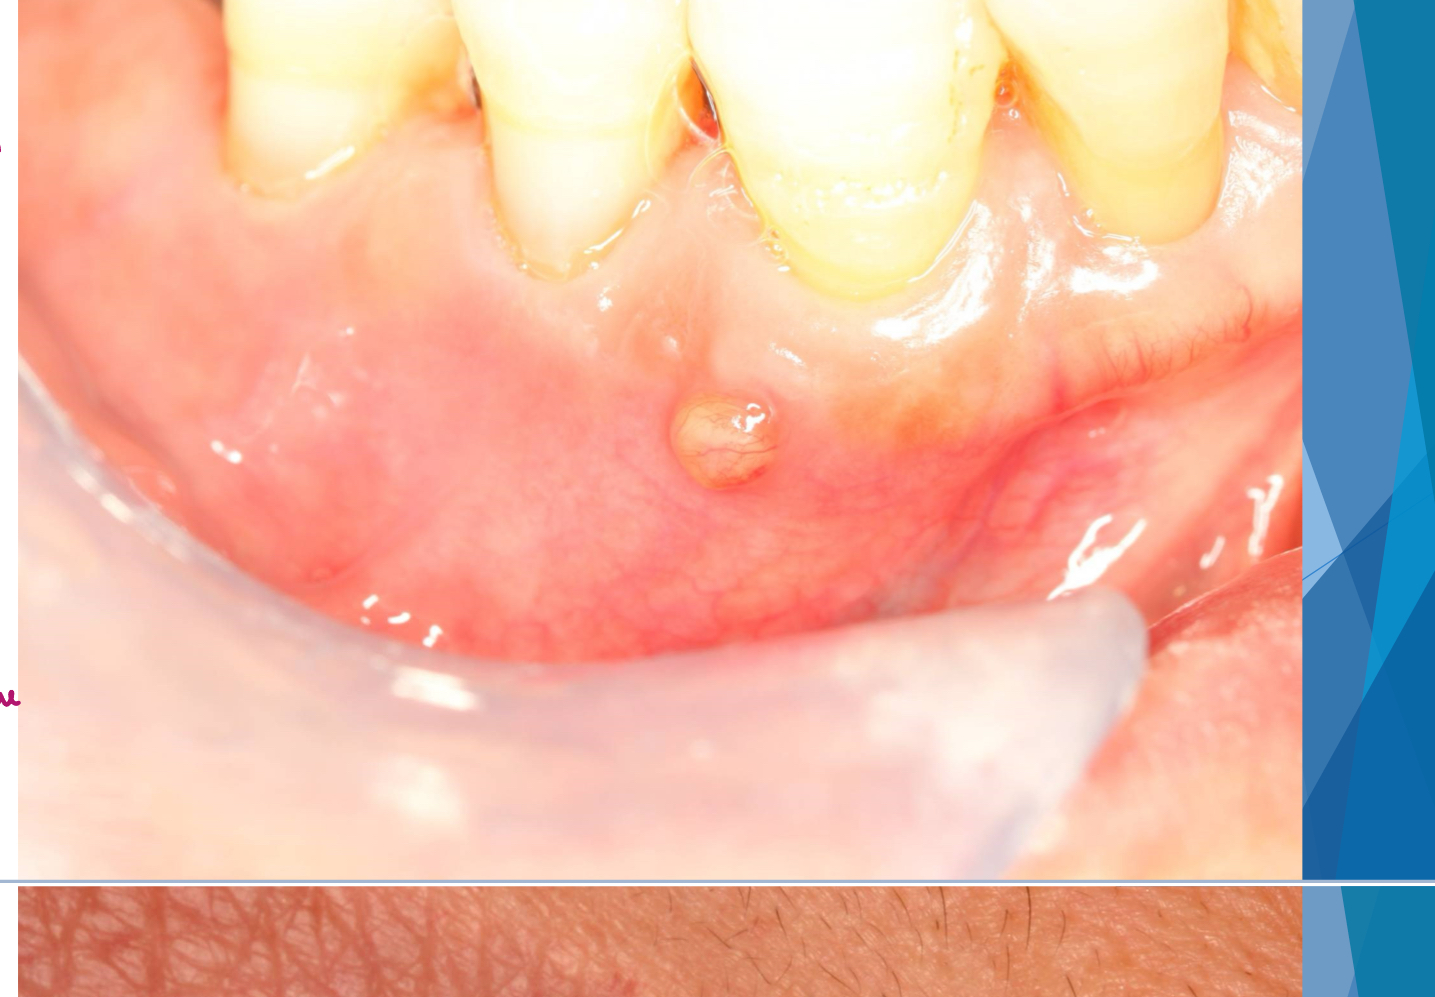

parulis aka gum boil

gum boil

parulis

which potential result of periapical inflammation?

inflamed granulation tissue at intraoral opening of sinus tract

classically dome-shaped yellow-pink papule; rarely hyperplastic soft tissue mass that may mimic pyogenic granuloma or other pathology ie exophytic hyperplastic perulis on adj tooth assocxiated w non-vital tooth

usually on gingiva facial to non-vital tooth

may or may not exhibit active suppuration